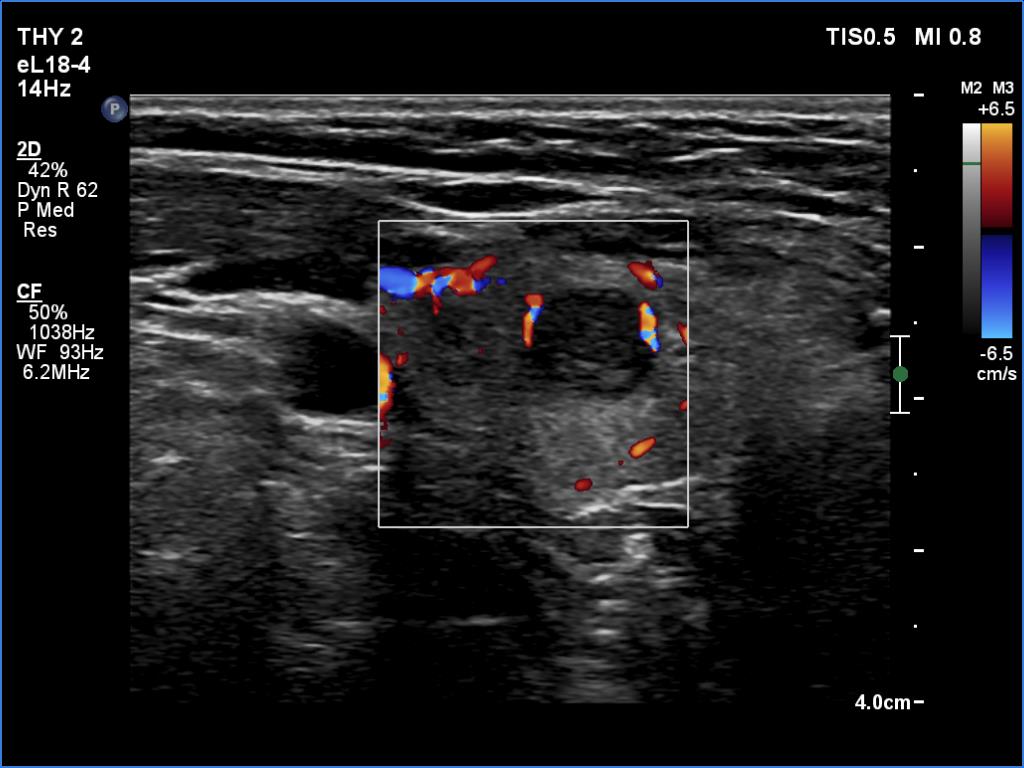

Ultrasonography. The thyroid was echonormal and presented several minimally-moderately hypoechoic areas. One of them, which was located in the central part of the right lobe was deeply hypoechoic and corresponded to pathological nodule. The other lesions seemed to be not true nodules but more active foci of thyroiditis.

Comment. It is worth comparing the deeply hypoechoic nodule with the other discrete lesions. The former has regular, sharp borders, and its echogenicity differs from other areas of the thyroid. These are the main clues of differentiation of a true nodule from a discrete lesion of Hashimoto's thyroiditis.